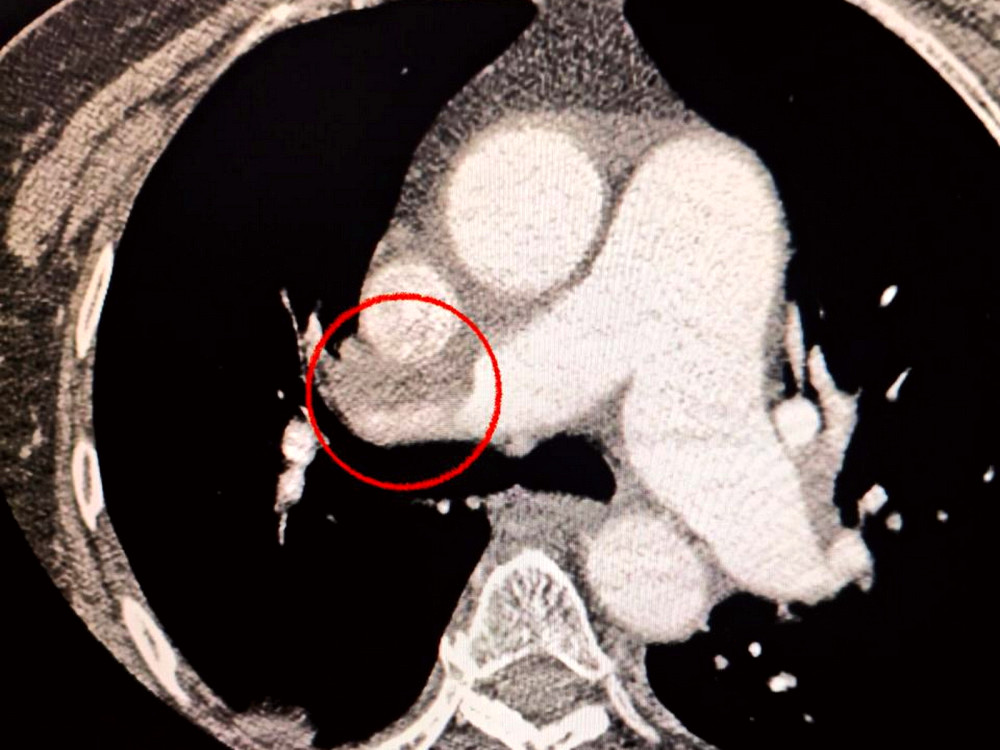

Пацієнтка, яка звернулася до медичного закладу з критичним інсультом, зазнала додаткового обстеження, яке виявило серйозні проблеми з легенями.

Діагноз ускладнився тромбоемболією, що спричинило необхідність в терміновому втручанні.

Команда спеціалістів вирішила провести операцію, яка об’єднала в собі лікування обох станів одночасно.